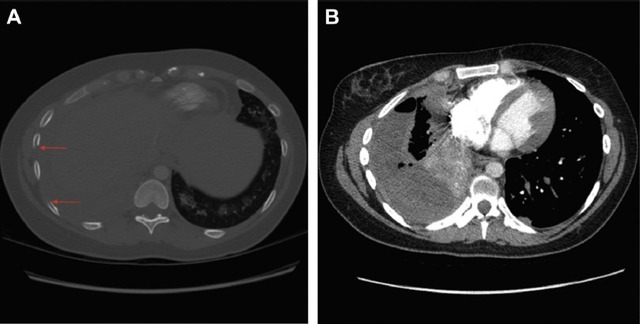

随后行胸腔穿刺术抽出血性胸水,胸水生化示葡萄糖 1.5 mmol/L,蛋白 51 g/L,乳酸脱氢酶 2212 U/L。胸水有核细胞总数 2100*106/L,仍以淋巴细胞为主(60%),格兰染色及培养均为阴性结果。胸片及胸部 CT 如图 1、2 所示。

图 2:肺 CT 血管成像显示无肺栓塞征象,但显示胸膜增厚,结节延伸至肋间隙,箭头处显示骨质破坏,此外,右中下肺野存在大量胸腔积液及明显肺不张。